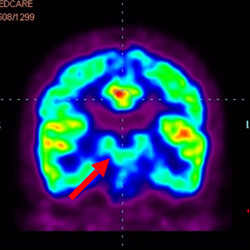

細(xì)胞治療前 PET CT 掃描顯示神經(jīng)組織中的藍(lán)/黑色區(qū)域,表明腦癱引起的大腦損傷。